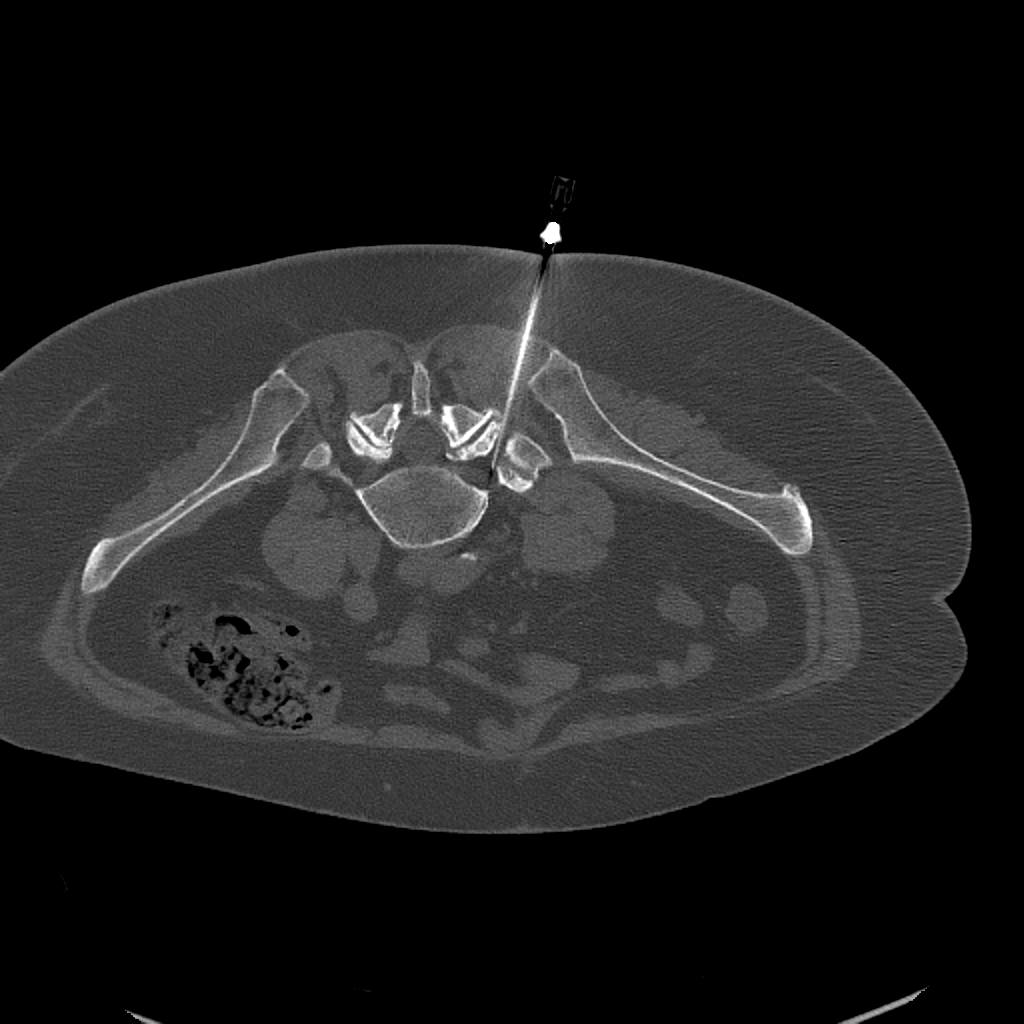

Blocaj țintit ghidat CT

Injecția de blocaj țintit este unul dintre cele mai eficiente instrumente în managementul conservator al durerii spinale. Există două tipuri principale, în funcție de faptul dacă rădăcina nervoasă sau articulația facetară cauzează simptomele.

Blocaj de rădăcină nervoasă ghidat CT: pe imagine se observă clar poziționarea precisă a acului lângă rădăcina nervoasă afectată

Blocaj radicular

Când perechea de nervi care iese dintre vertebre este sursa durerii — de exemplu din cauza herniei de disc sau stenozei spinale — este necesară terapia injecțională de blocaj al rădăcinii nervoase. În timpul procedurii, o cantitate minimă de anestezic local și steroid antiinflamator este livrată lângă rădăcina nervoasă afectată.

Targetarea precisă a acului este verificată cu CT sau fluoroscopie. Amorțeala sau slăbiciunea temporară pot apărea datorită anestezicului — acesta este un fenomen natural care se rezolvă de obicei în câteva ore.